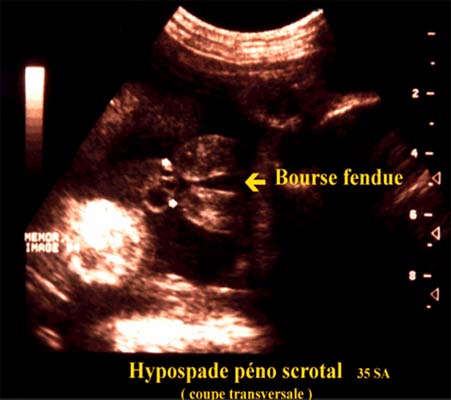

L’hypospade proximal ou péno scrotal est plus complexe et plus grave.

Dans sa forme majeure les bourrelets labio scrotaux ne fusionnent pas ce qui donne un aspect de bourse fendue, le pénis est de petite taille l’ensemble évoquant un sexe féminin.

L’existence des testicules dans les bourrelets est une aide au diagnostic.

Si les testicules restent dans les canaux inguinaux le tableau constitue un piège diagnostic et fait porter un diagnostic erroné de sexe féminin.